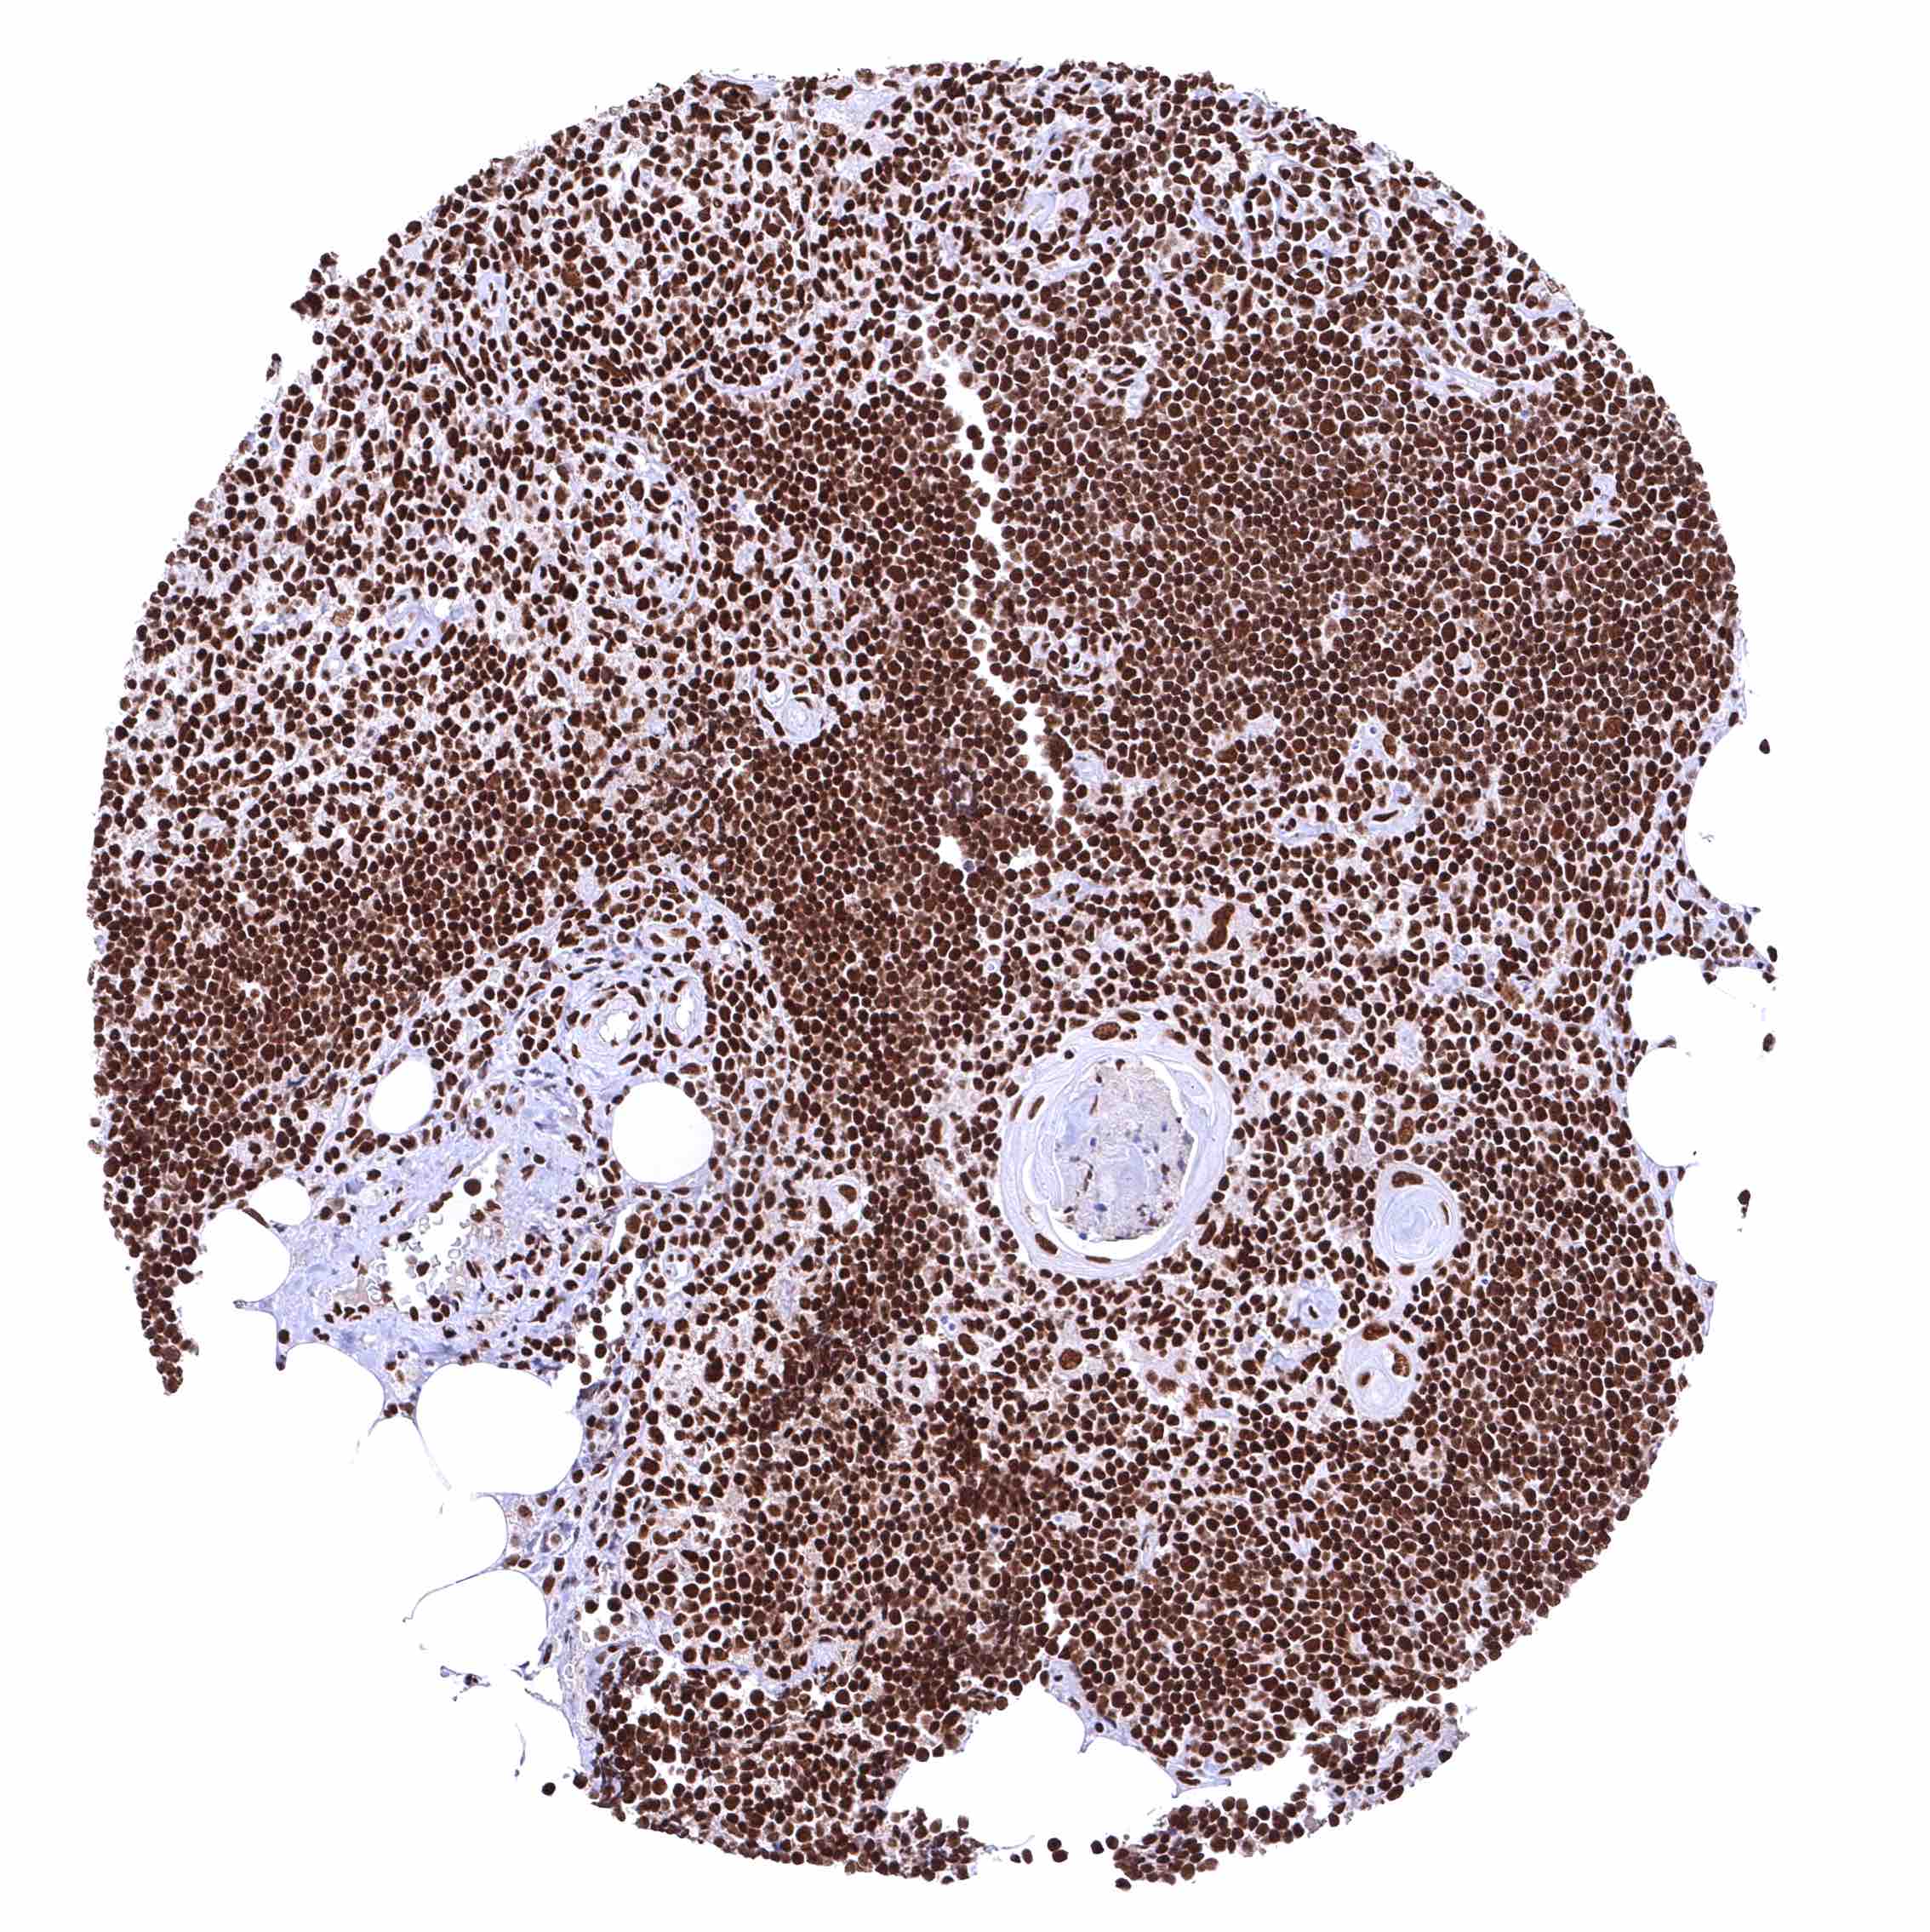

Lymph node – Strong nuclear BRD4 staining of all cell types.